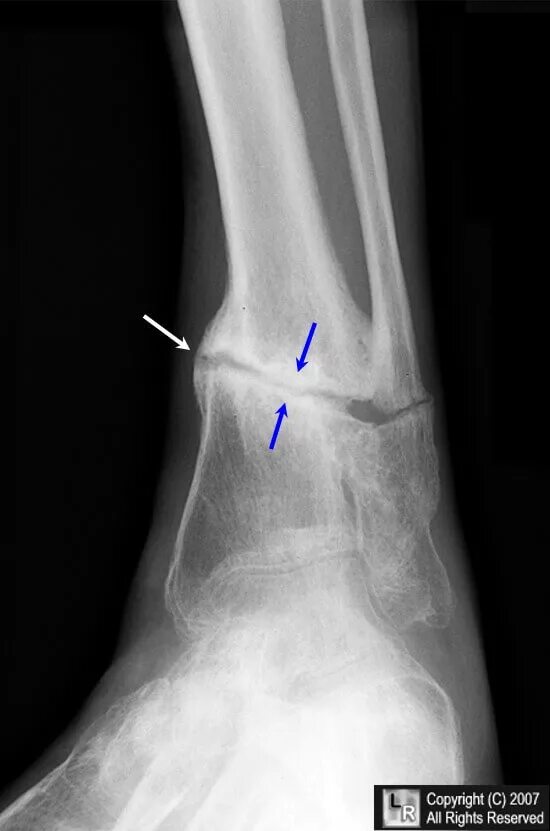

Перелом дефект